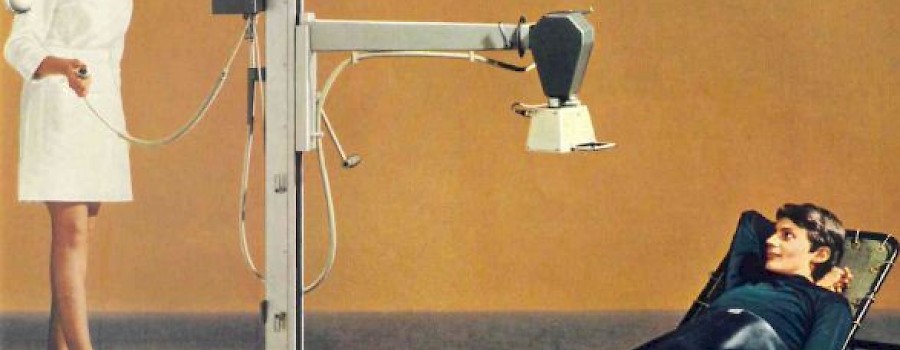

Primäreffekte direkt ionisierender Strahlung

Primäreffekte direkt ionisierender Strahlung übertragen durch Stoßprozesse Energie auf die Hüllenelektronenund entfernen diese aus dem Elektronenverband. Dabei verlieren die Teilchen bei jedem Stoß kinetische Energie.